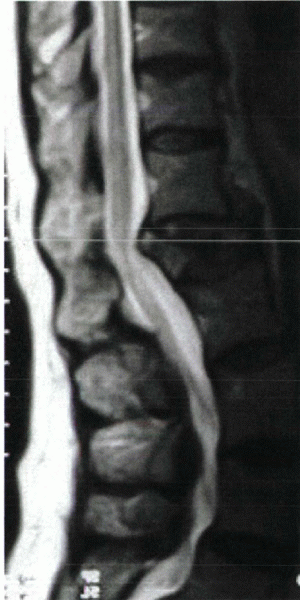

![]() |

Figure 24-1

A 74-year-old man with secondary osteoporosis and degenerative scoliosis complained of severe midback pain and balance difficulties after a fall from a stepladder. Anteroposterior radiograph (A) shows osteopenia and a lateral vertebral compression fracture. Pain failed to respond to 4 weeks of management with narcotics and a Cash brace, and MRI was obtained. T1-weighted image (B) shows decreased signal intensity in T12. Increased signal was noted on T2 image (not shown). The patient was point tender over this level. Based on his continued pain and functional limitation, he was offered kyphoplasty. Anteroposterior fluoroscopic image during early balloon inflation (C) shows differential inflation on the more compressed side. The patient reported continued improvement for the next 2 weeks and ultimately returned to his baseline 3/10 visual analogue pain scale pain level. He was started on alendronate (Fosamax), calcium, and vitamin D. |

The edema seen in acute fractures is reflected by increased signal on

time (see Fig. 24-1B). MRI may reveal several